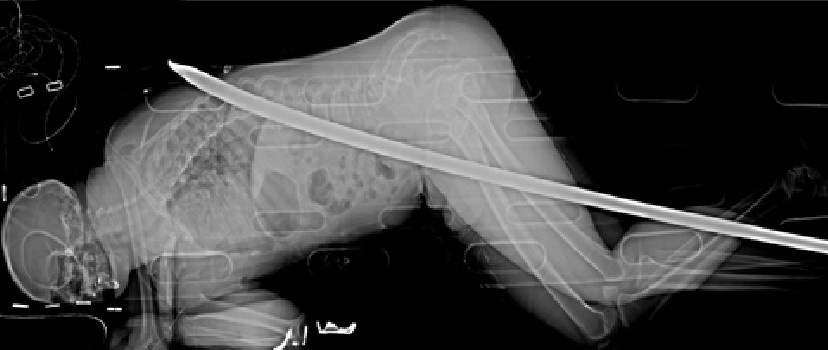

▲南非一名工程師遭180公分長鐵棍貫穿身體 ,卻在3周後奇蹟似康復出院。(圖/翻攝自Netcare Milpark醫院臉書/下同)

南非卡雷頓維爾(Carletonville)一名工程師3年前在礦坑內滑倒,遭到一根長約180公分的鐵管插進體內,從大腿一路貫穿身體,最後從背部刺出。男子緊急送醫治療後卻奇蹟似地在3周後健康出院,最近更要以跑者的身分參加87公里的超級馬拉松比賽,以證明身體狀況恢復良好。

工程師迪韋特(Daniel de Wet)於2015年1月10日和同事一起深入地下3公里的地下礦場視察,卻在處理工事時意外滑倒,手上的工程工具從腹股溝部位插入身體。當下駭人的情景瞬間讓同事嚇傻了,迪韋特卻說,「一開始並不覺得很痛,我還要先安撫他的情緒,並指示他透過對講機向外求援。」

「我變成了全場最冷靜的人」迪韋特回憶起充滿波折的救援過程,醫護人員不知道要如何將身上插著鐵棍的傷者抬上直升機,還必須先拆除機上的設備,以騰出更多空間。到院緊急治療後,醫師宣布迪韋特的腎臟和大腸都遭破壞,醫務人員更指出,「他的傷勢非常可怕、嚴重。」